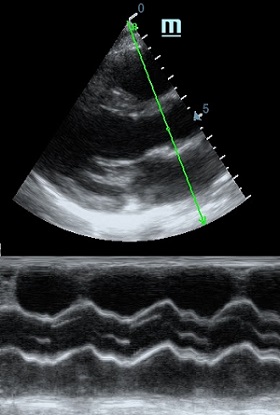

Но как же провести стандартные измерения в М-режиме, если мы его не использовали? На помощь приходит функция Free Xros M – анатомический М-режим. Имея записанную в память прибора видео петлю, мы можем провести линию М-режима в любом месте, при этом корректируя изначально не оптимальный угол.

Возможности применения функции многогранны: от измерения толщины стенок левого желудочка, движения створок митрального клапана и кооптации нижней полой вены до оценки сократимости миокарда как глобально, так и по сегментам.